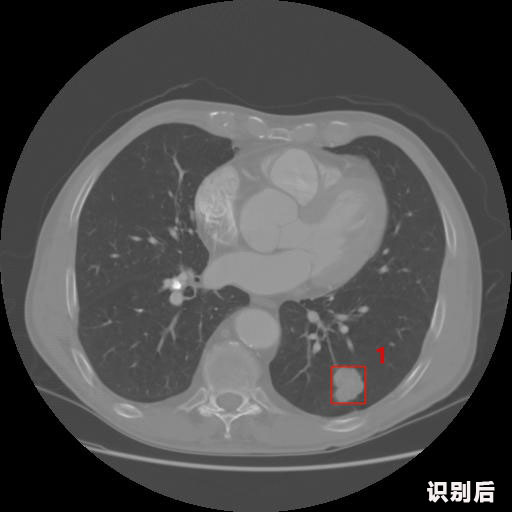

英特健康A(chǔ)I深度學(xué)習(xí)醫(yī)療圖像識別系統(tǒng)案例_胸部CT

04.jpg

報告:

1.發(fā)現(xiàn)肺結(jié)節(jié)的可能性為95.56%---位于框指數(shù)位置:[331.70554 366.13406 365.21707 403.96234]